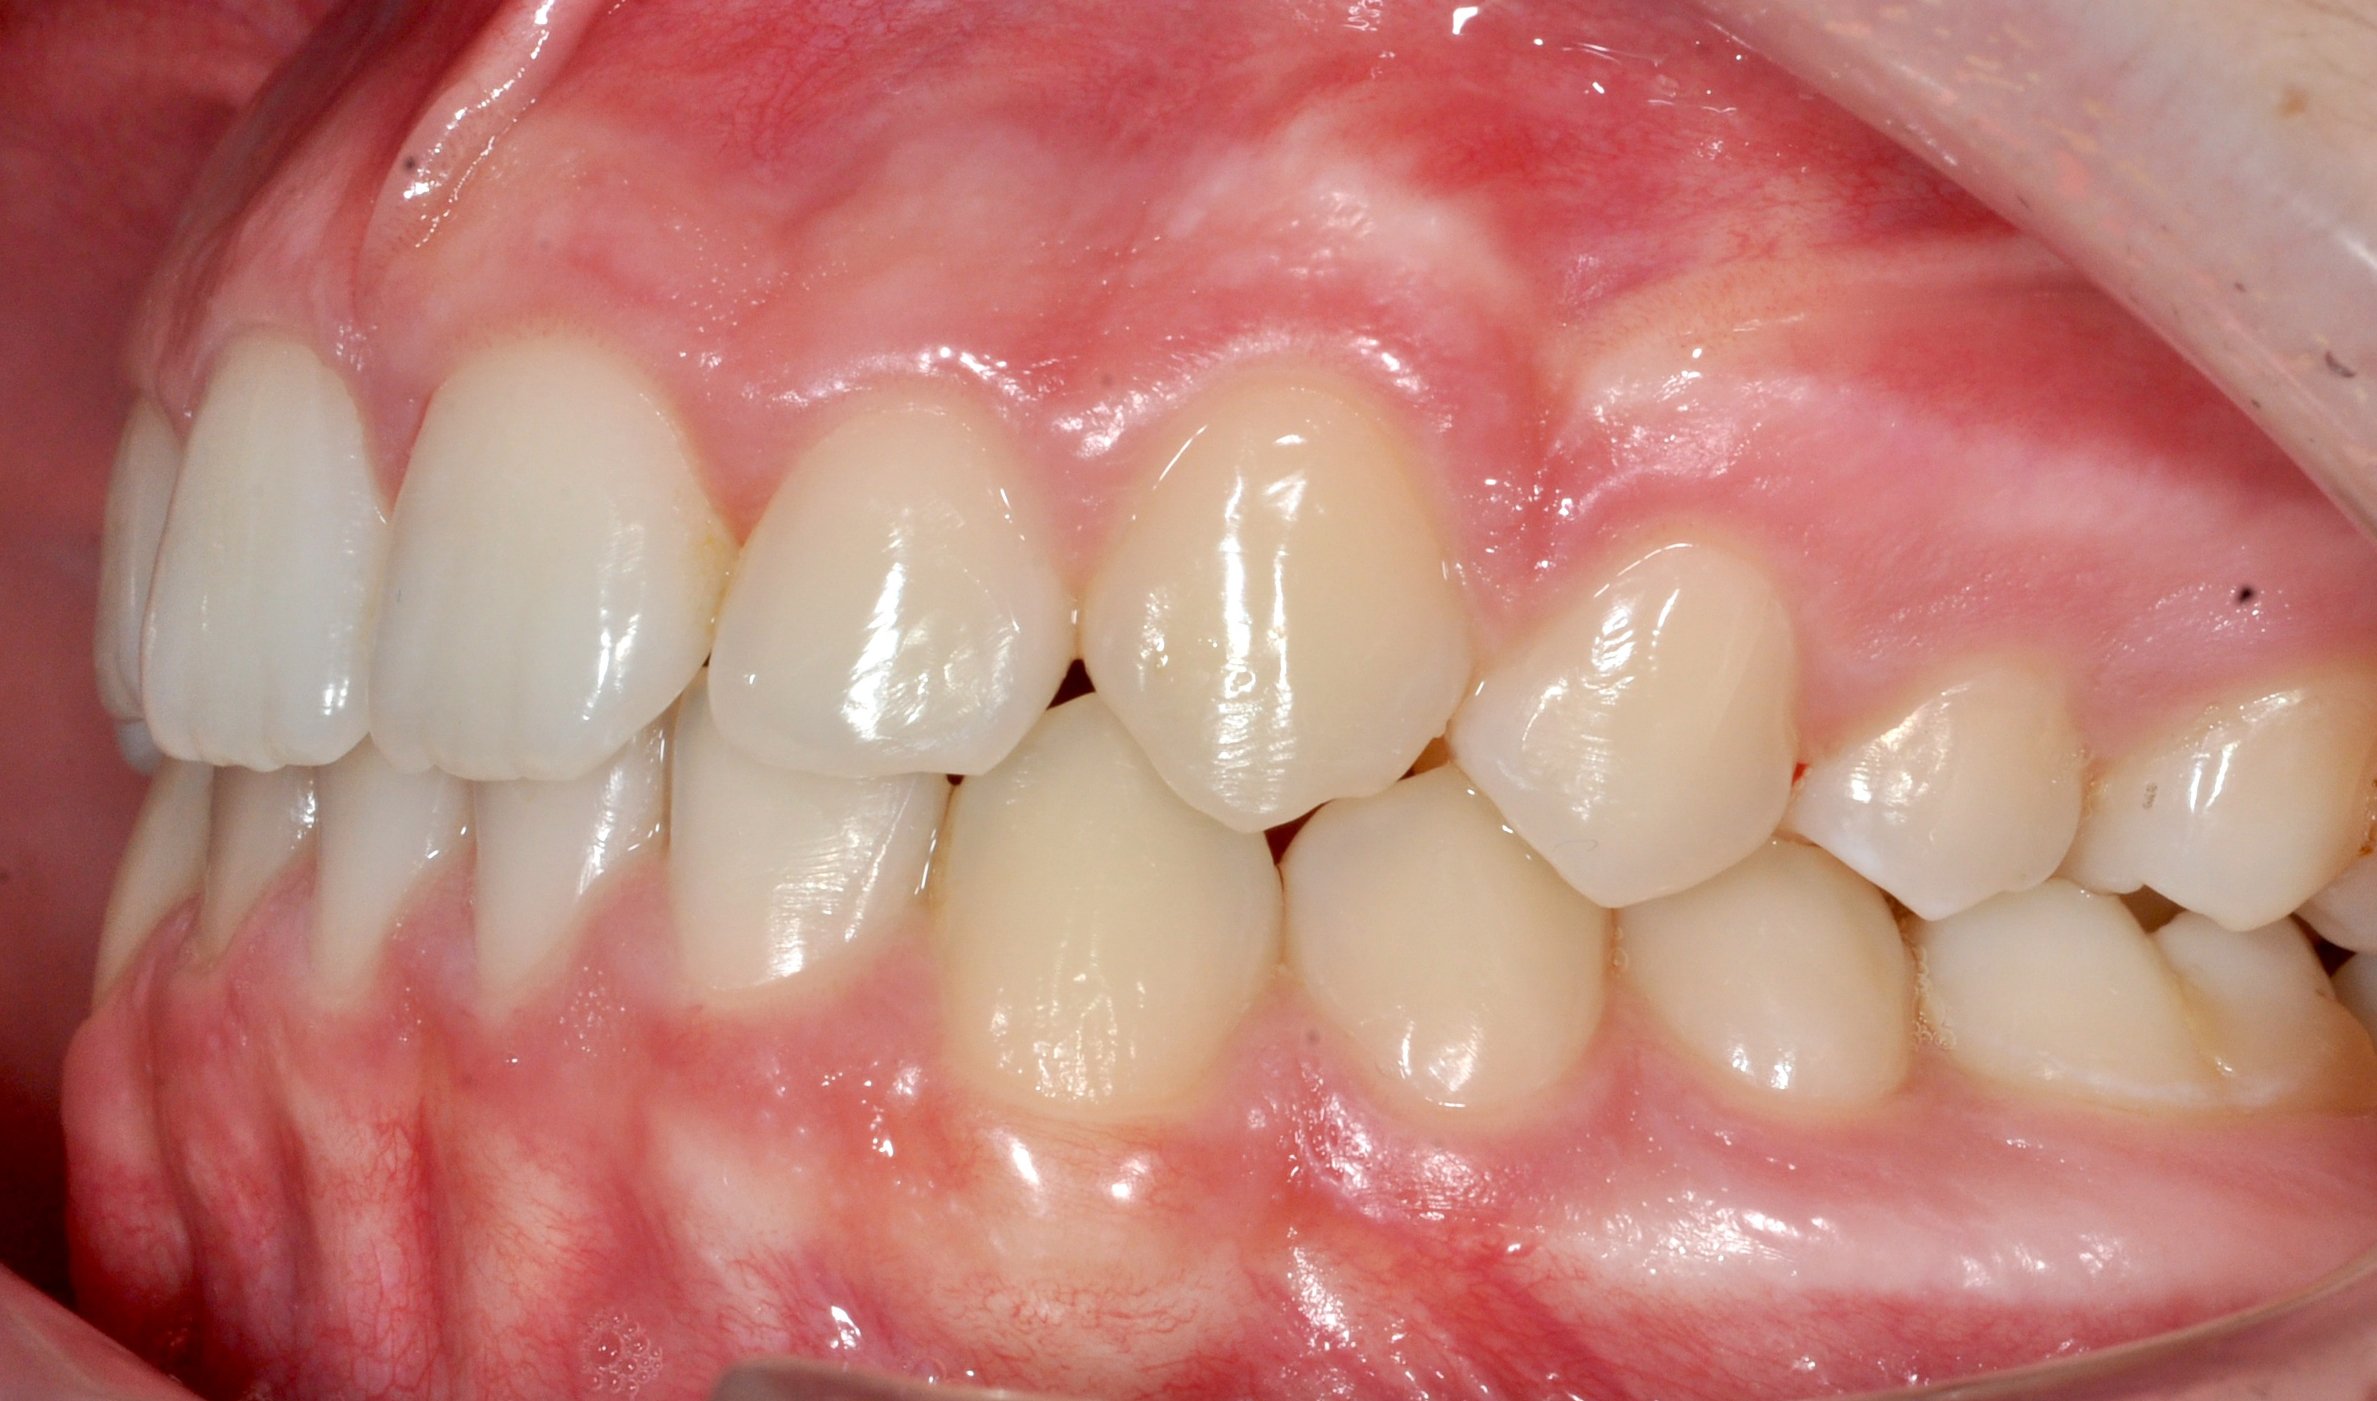

Caso 2 – Allineatori trasparenti in paziente adulto

Il trattamento con allineatori trasparenti ha permesso, in circa 18–20 mesi, di riallineare i denti, ampliare le arcate e migliorare la chiusura del morso, ottenendo un risultato stabile, funzionale ed esteticamente armonioso.

DOPO